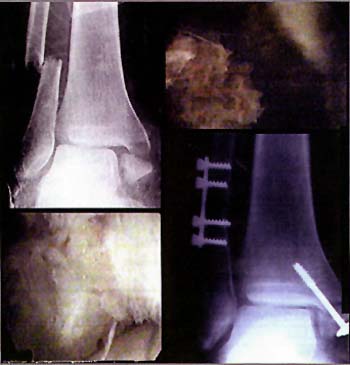

Paso I :reduccitin video asistida y control fluoroscopico.

Paso 2: colocacion de alambre guia de tornillo canulado

Caso em- Sexo femenino - 62 años.

Paso 3: perforacion de cortical con mecha canulada.

Paso 4: colocacion de tornillo canulado en Mal.Interno

Caso AM sexo femenino - 14 años